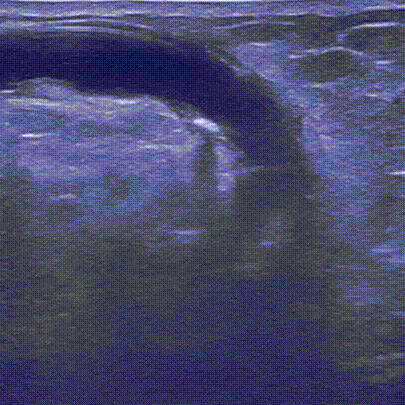

吻合口血流信号丰富。